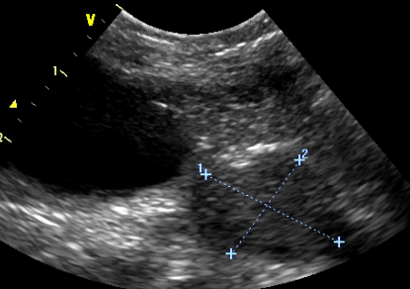

How does the overall echogenicity compare to the normal prostate?

What is the liekly differential?

Heterogenous

More echogenic

Bigger too

Diagnosis:

BPH

Cant rule out infection = not many cysts